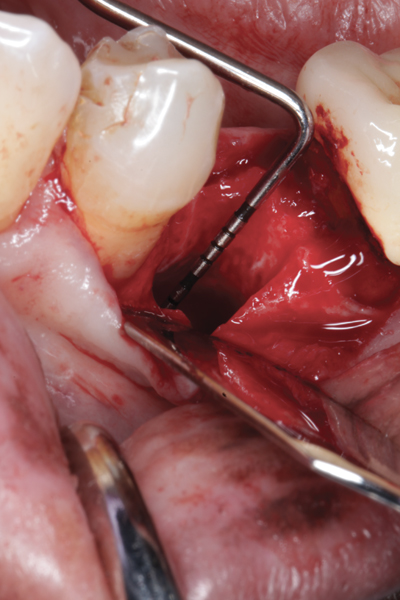

Fig 2. Buccal flap elevated exposing buccal plate defect.

Figure 2

The four presented cases shown in Figure 1 through Figure 25 were all treated in a similar manner as outlined in detail in the captions for the first case (Figure 1 through Figure 11). In all four cases, teeth with pathosis were removed, buccal and lingual flaps were elevated, and sites were surgically debrided. A Cytoplast d-PTFE barrier was sized and inserted usually under the buccal flap, the bone graft was added, the barrier was then tucked under the lingual flap, and the flaps were sutured. Bone grafts were used in all of the cases, because buccal bony plates were resorbed and the bone graft helped support the barrier.